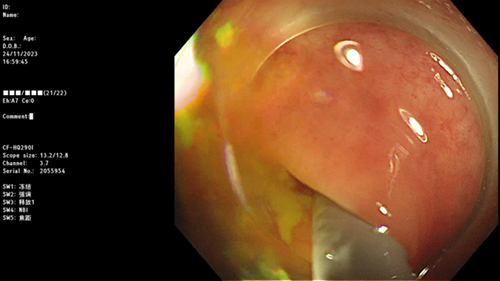

结肠镜下看到阑尾开口被冲出的粪石

冲洗干净后的阑尾腔